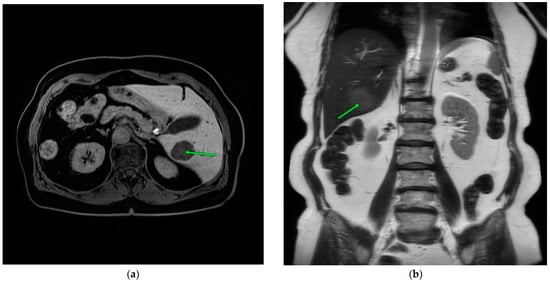

Due to the detection of a hypermetabolic lesion in the liver in the follow-up PET/CT scan (lesion 35 mm SUV max 6.1 in the right lobe), the decision was made to perform an abdominal MRI with contrast, which confirmed the presence of a lesion in segment 6 of the liver, 17 mm in size, with a moderately increased signal at T2 and T2fs, a decreased signal at T1 with weak heterogeneous contrast enhancement, and limiting diffusion of a non-characteristic lesion, more suggestive of a malignant lesion. Observation in the form of regular imaging studies was decided upon. Over the following months, a gradual regression of the lesion size to a maximum of 10 mm was observed, followed by a new increase up to 57 × 46 mm.

A percutaneous liver biopsy was performed (Figure 1). The histopathological examination described a hepatic tissue with infiltration of plasma cell myeloma. IHC: CD38+, CD138+, chromogranin−, synaptophysin−, and Ki67+ in approximately 80% of cells. The results of the biopsy confirmed that the lesion, which seemed to be an independent tumor, was in fact the outcome of the underlying disease.

An additional CT scan was performed after the biopsy, which peripherally showed a single, fairly well-demarcated oval nodular mass measuring approximately 57 × 46 mm with strong heterogeneous enhancement, and a relatively rapid washout in the venous/delayed phase was detected in segment VI, causing peripheral perfusion abnormalities and accentuation of the intrahepatic bile ducts (Figure 2a). The lesion was vascularized by a prominent branch of the right hepatic artery (Figure 2b).

Figure 2. Abdominal MRI. Green arrows point the lesion (a,b).